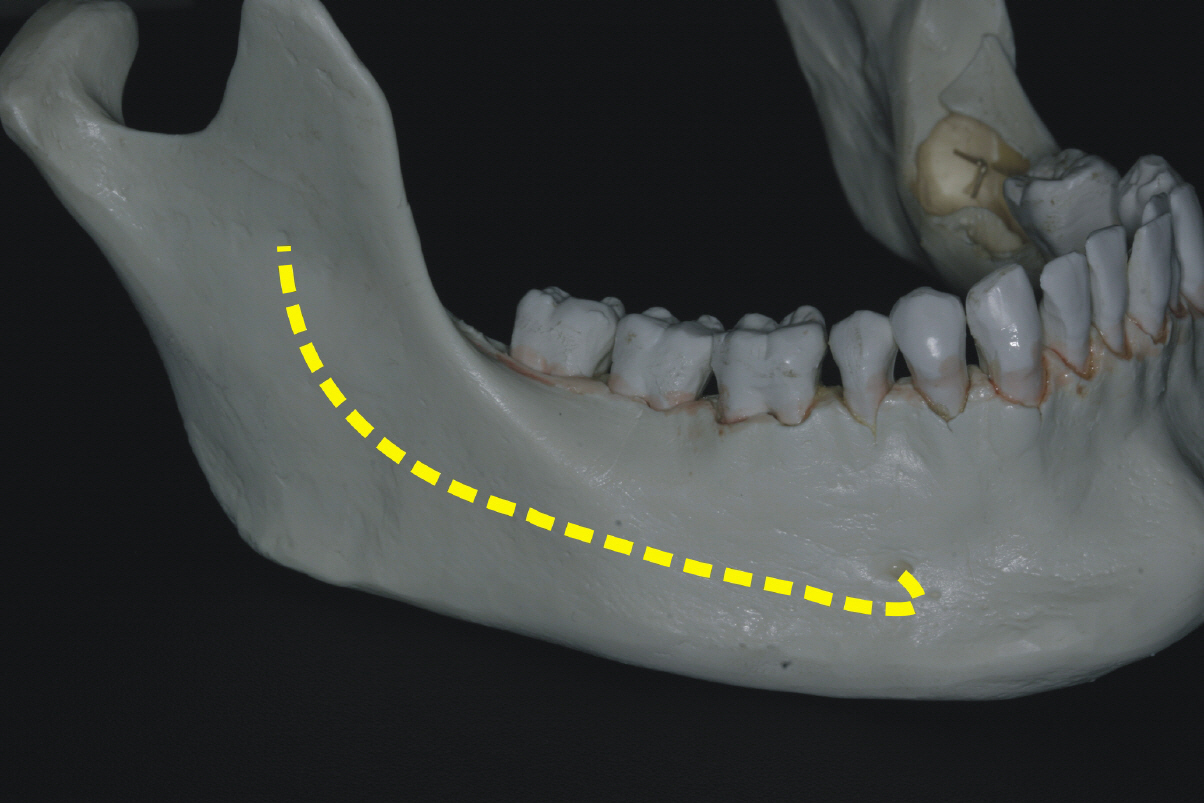

Im hinteren bzw. seitlichen Unterkieferknochen verläuft ein sehr sensibler Nerv (sensibel=Nerv, der für die Gefühlsempfindung zuständig ist), welcher die untere entsprechende Lippenseite mit Gefühl versorgt.

Bei der Implantation in Nervnähe kann es beispielsweise alleine schon durch das Abhalten der zu schützenden Strukturen zu einer vorübergehenden Reizung des Nervs kommen. Dies äußerst sich in aller Regel so, dass ein dumpfes oder taubes Gefühl in der Lippenregion ist, welches ein paar Tage bis Wochen anhalten kann. In einzelnen Fällen kann auch ein „kribbeliges“ Gefühl in der Lippe sein, also eine Gefühlsüberempfindung. Wird der Nerv beispielsweise durch zu tielfes bohren des Implantatlagers durchtrennt, so kann ein dauerhaft taubes Gefühl in der Lippe verbleiben.

Vermutlich fehlende Planung und Erfahrung führten in dem Fall oben zur Auswahl eines deutlich zu langen Implantates mit Verletzung des Unterkiefernervs. Der Nervverlauf ist durch die roten Linien gekennzeichnet, die obere entspricht dem Nervdach, die untere dem Boden des Nervkanals. In diesem Fall ist eine sofortige Entfernung (sogenannte Explantation) des des Implantates erforderlich.